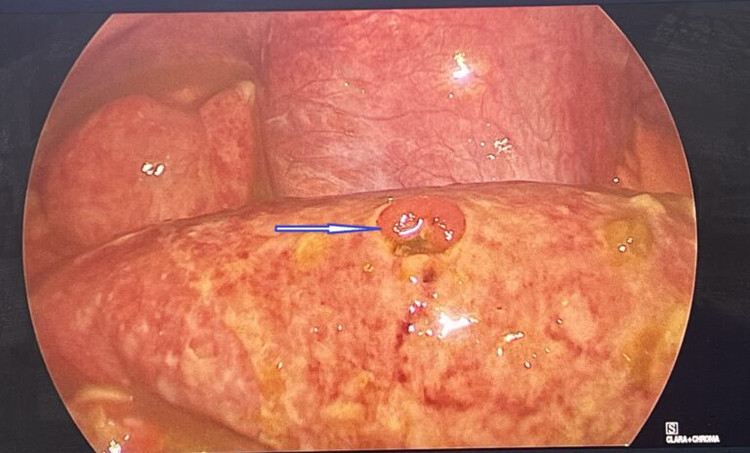

Hình ảnh nội soi trước phẫu thuật: ruột non vỡ |

Hình ảnh nội soi trước phẫu thuật: ruột non vỡ